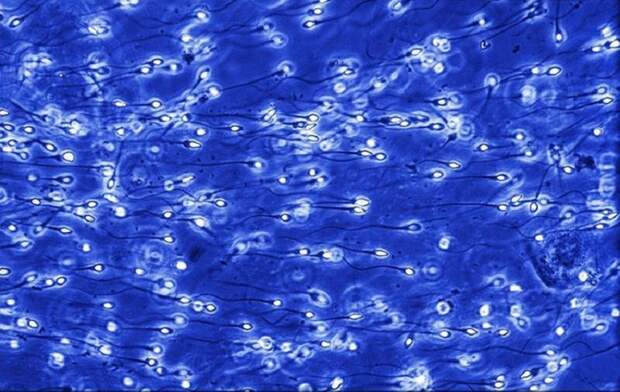

А это миллионы сперматозоидов направляются к шейке матки.

А это миллионы сперматозоидов направляются к шейке матки.  Дальше сперматозоид двигается по маточной трубе к яйцеклетке.